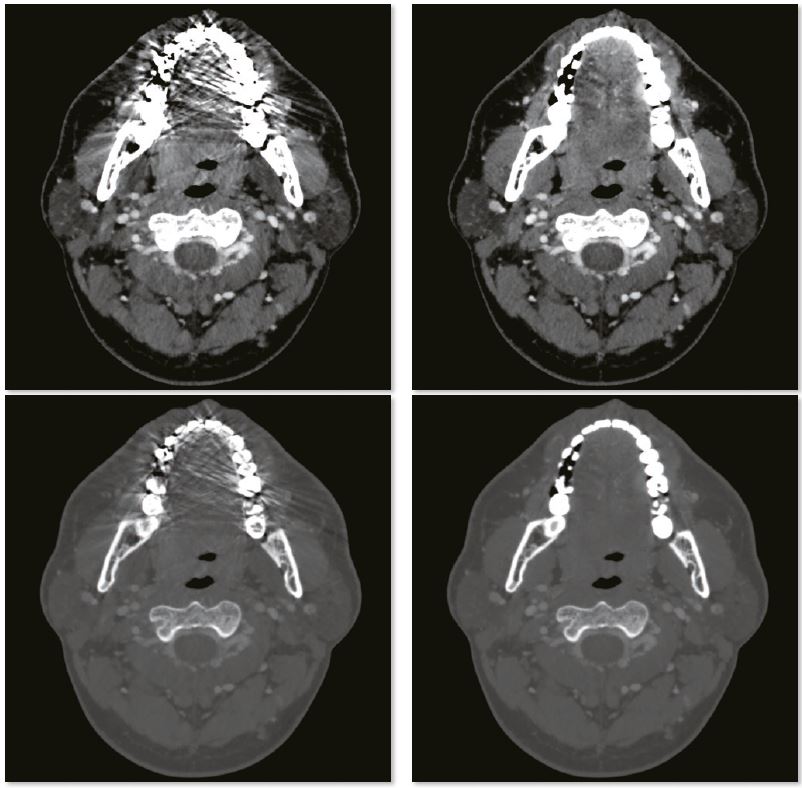

Усунення артефактів від зубних пломб

Артефакти з амальгамних пломб повністю усуваються за допомогою реконструкції SEMAR, що дозволяє точно оцінити прилеглі м’які тканини. На цьому постконтрастному скануванні кісток обличчя видно невелику пухлину, яка прилягає до нижньої щелепи.

3D зображення нижньої щелепи

Звичайне зображення

Зображення з SEMAR